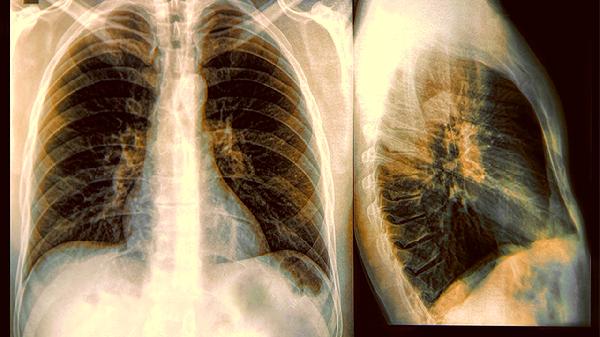

二、四个危险特征要当心

1、边缘不规则

良性结节边缘通常光滑整齐,像颗圆润的珍珠。如果出现毛刺状、分叶状或锯齿状边缘,就要引起重视了。

3、密度不均匀

CT显示结节内部有空洞、钙化点分布不规则,或者出现“支气管充气征”,都可能是恶性的表现。